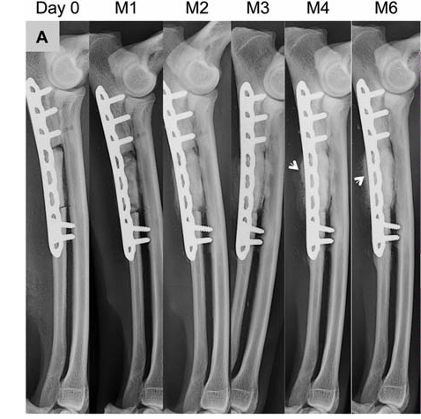

手术后进行X线分析骨缺损位置大小是否合适,植入的材料是否固定良好。后续可定期观察骨缺损修复以及材料融合情况。

犬尺骨缺损骨修复监测

数据来源:DOI:10.1002/jbm.a.36384